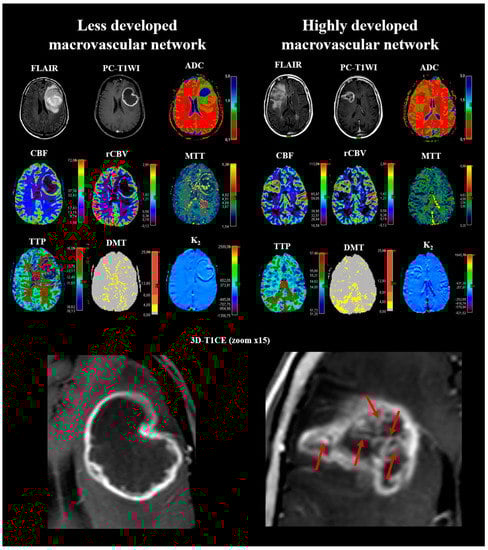

2.1. Determination of the Cutoff for Number of Vessel-Like Structures in Glioblastoma

4.4. Qualitative Image Analysis